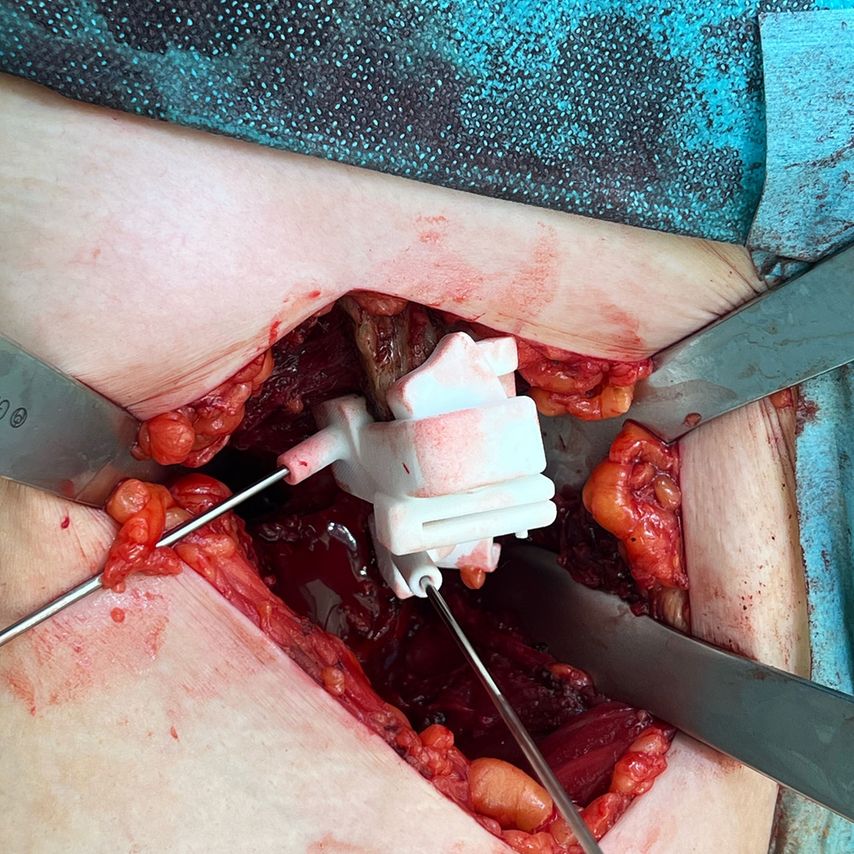

Die Verwendung einer patientenspezifischen Instrumentation (PSI) auf Basis einer 3D-Modell-Planung ist bei knienahen Umstellungsosteotomien in der Orthopädie bereits ein gängiges Verfahren. Dieses Konzept kann nun teilweise auch bei der PAO angewendet werden. Dabei wird das knöcherne Becken präoperativ in der Computertomografie erfasst und am 3D-Modell werden die optimalen Schnittführungen um die Hüftgelenkspfanne geplant. Mittels eigener Software kann das Acetabulum am Monitor auf ein Grad genau in allen Ebenen gedreht werden. Auch eine notwendige Translation des Fragments kann beurteilt werden. In der Korrekturposition des Pfannenfragments können zusätzlich bereits die Positionen und Längen der Schrauben errechnet werden. Auf Basis dieser Planung werden PSI-Schnittblöcke und Korrekturblöcke produziert und für den Eingriff sterilisiert.

Bis jetzt gibt es zu dieser Thematik nur allgemeine anekdotische Berichte in der Literatur.6 Erste intraoperative Anwendungen von PSI-Schnittblöcken für die PAO an unserer Abteilung waren aber vielversprechend. Natürlich verlangt das Anlegen von Schnittblöcken und Korrekturblöcken mehr Weichteilrelease von den knöchernen Strukturen und unter Umständen auch einen längeren Hautschnitt mit größeren Expositionsflächen am Becken. Zudem haben wir bisher aufgrund unseres alleinigen OP-Zugangs von ventral nur Schnittblöcke für die Ilium-Osteotomie und den proximalen Anteil des Verbindungsschnittes verwendet. Eine exakte Schnittplanung in dieser Region ist aber wichtig, um hier nach vollständiger Mobilisierung des Pfannenfragments den Korrekturblock exakt so zu positionieren, dass sich das Pfannenfragment in der gewünschten Abduktions-, Flexions- und Rotationsstellung einstellen lässt. In dieser Position können über die vorgefertigten Bohrhülsen im Korrekturblock gleich die Schraubenkanäle vorgebohrt werden. Eine zeitliche Verzögerung durch die Verwendung der Schnittblöcke konnten wir insgesamt nicht beobachten.